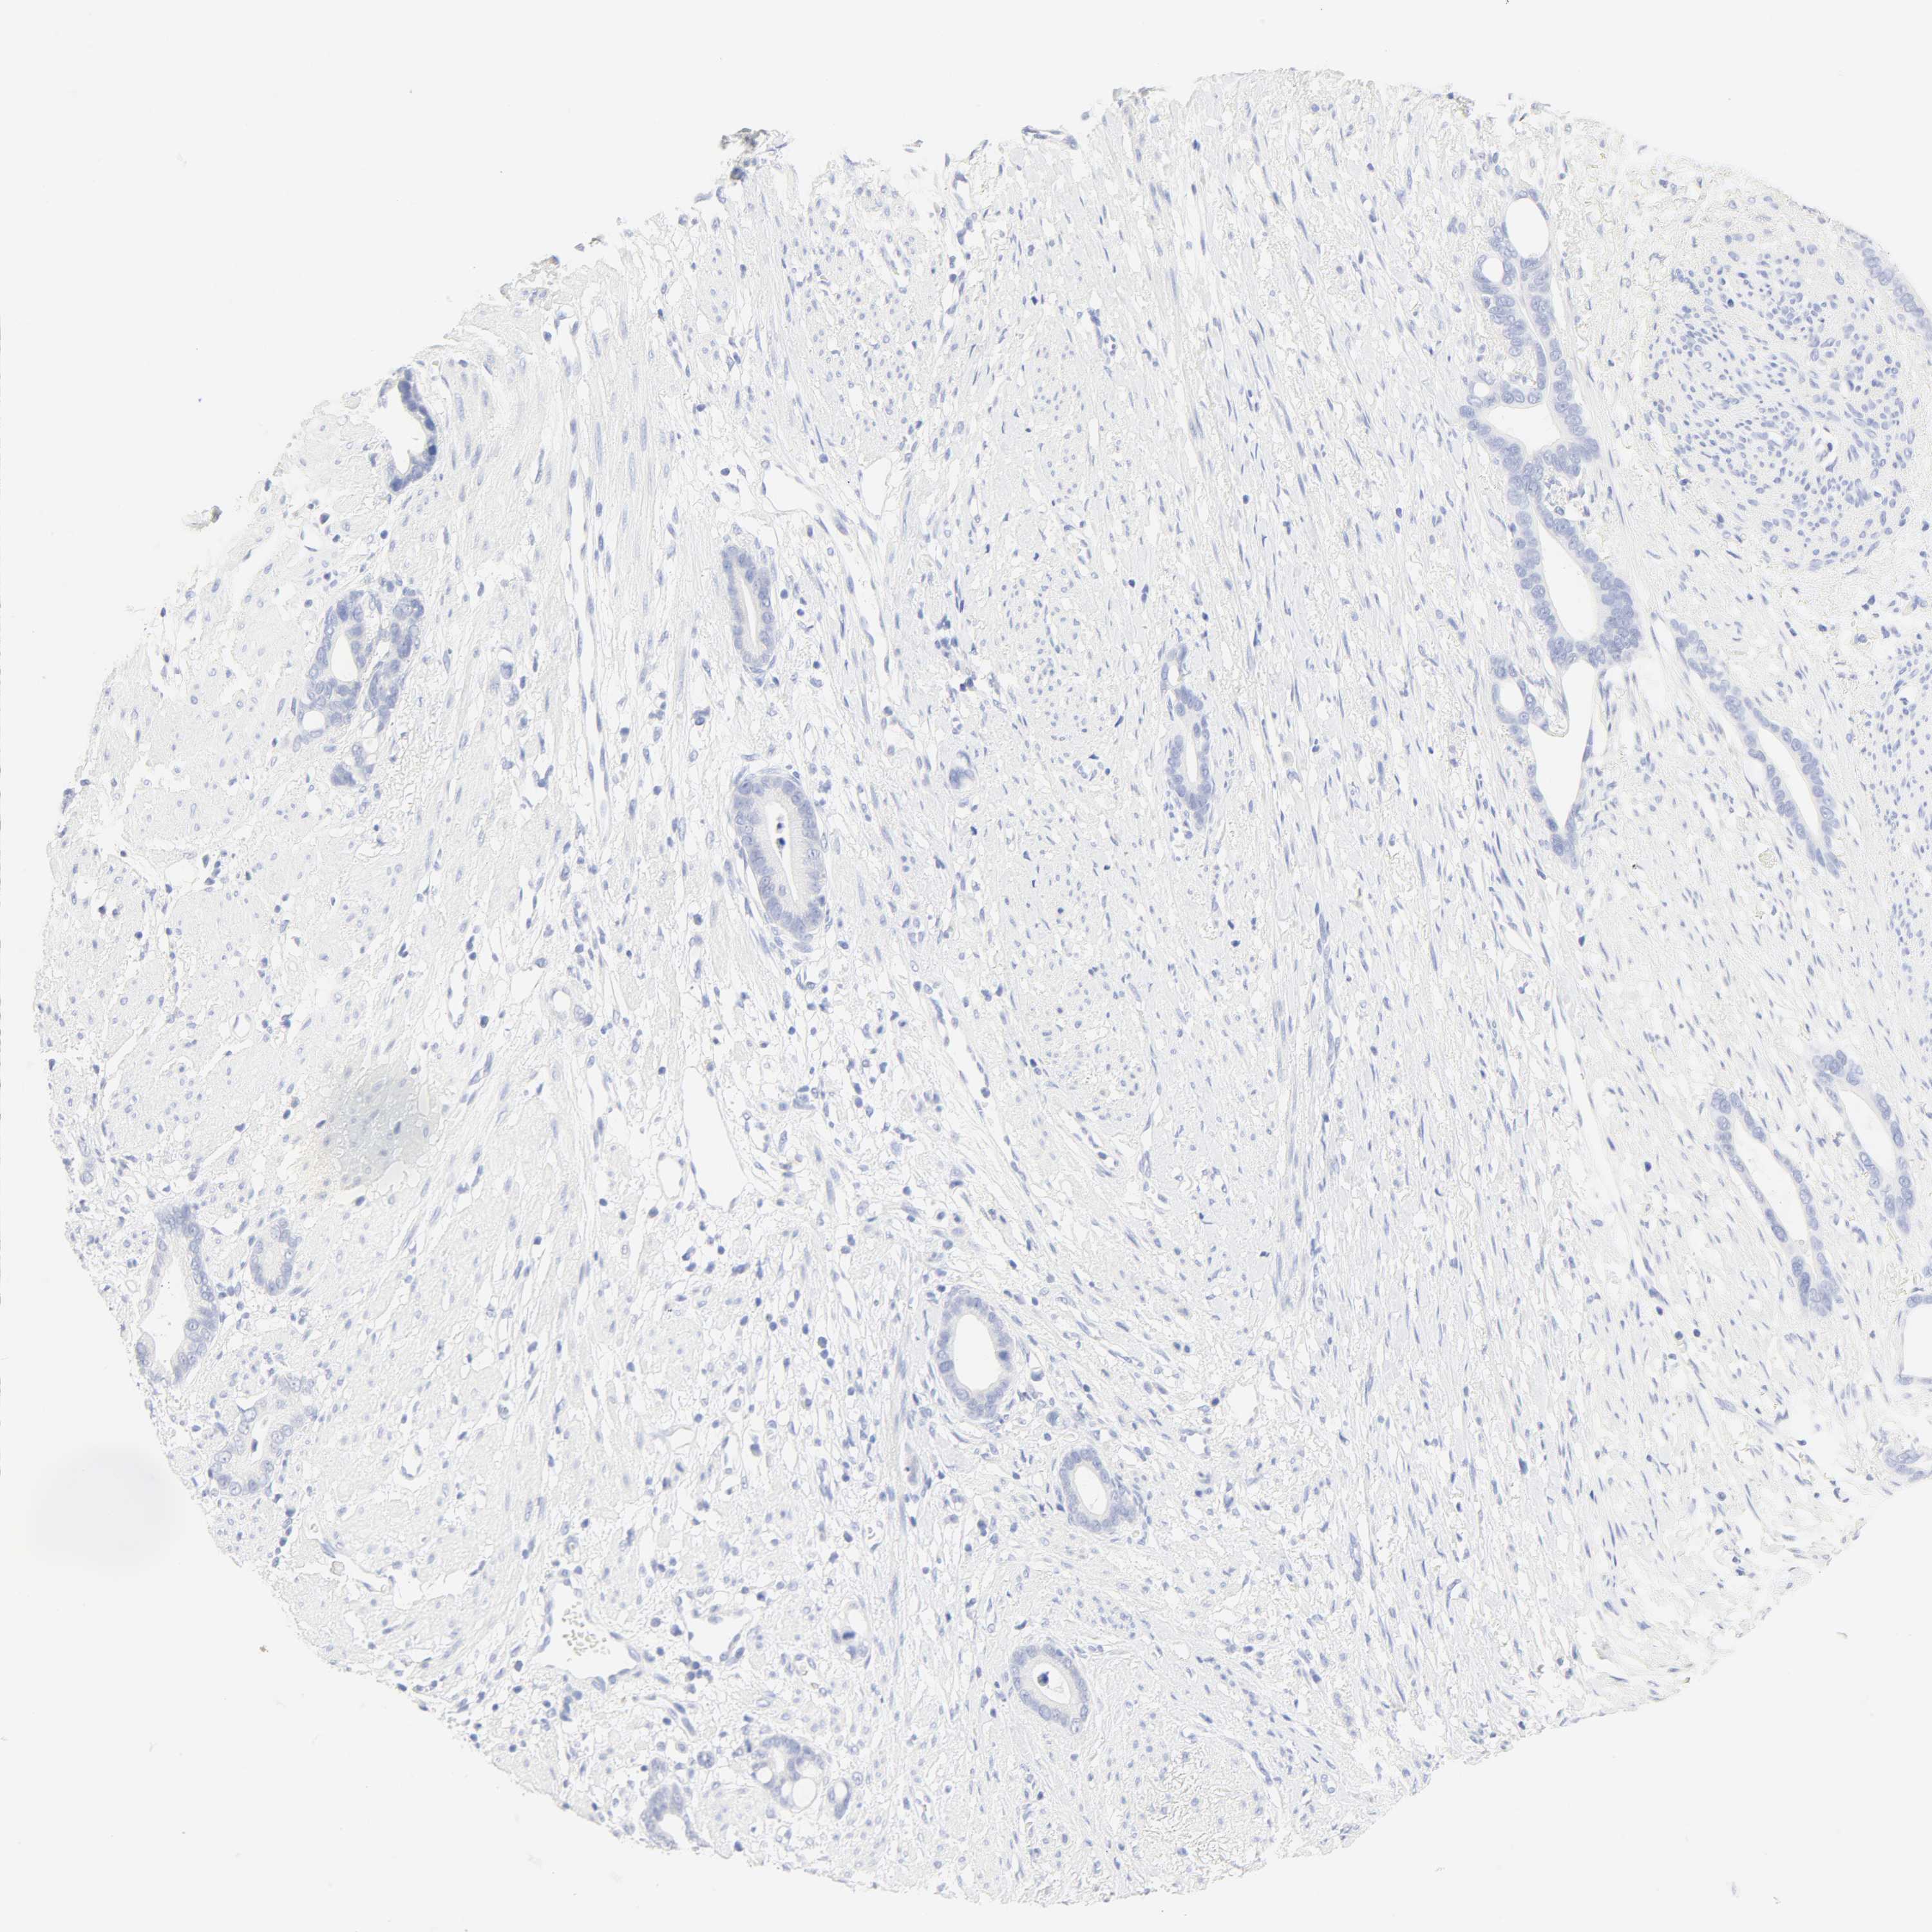

STOMACH CANCER - Protein expressioni

A mouse-over function shows sample information and annotation data. Click on an image to view it in a full screen mode. Samples can be filtered based on level of antibody staining by selecting one or several of the following categories: high, medium, low and not detected. The assay and annotation is described here.

Antibody stainingi

Antibody staining in the annotated cell types in the current human tissue is reported as not detected, low, medium, or high, based on conventional immunohistochemistry profiling in selected tissues. This score is based on the combination of the staining intensity and fraction of stained cells.

Each image is clickable and will lead to virtual microscopy that enables deeper exploration of all samples and also displays staining intensity scores, fraction scores and subcellular localization as well as patient and tissue information for each sample.

Antibody HPA004943

Antibody HPA050892

Staining

High

Medium

Low

Not detected

Adenocarcinoma, NOS

Adenocarcinoma, High grade